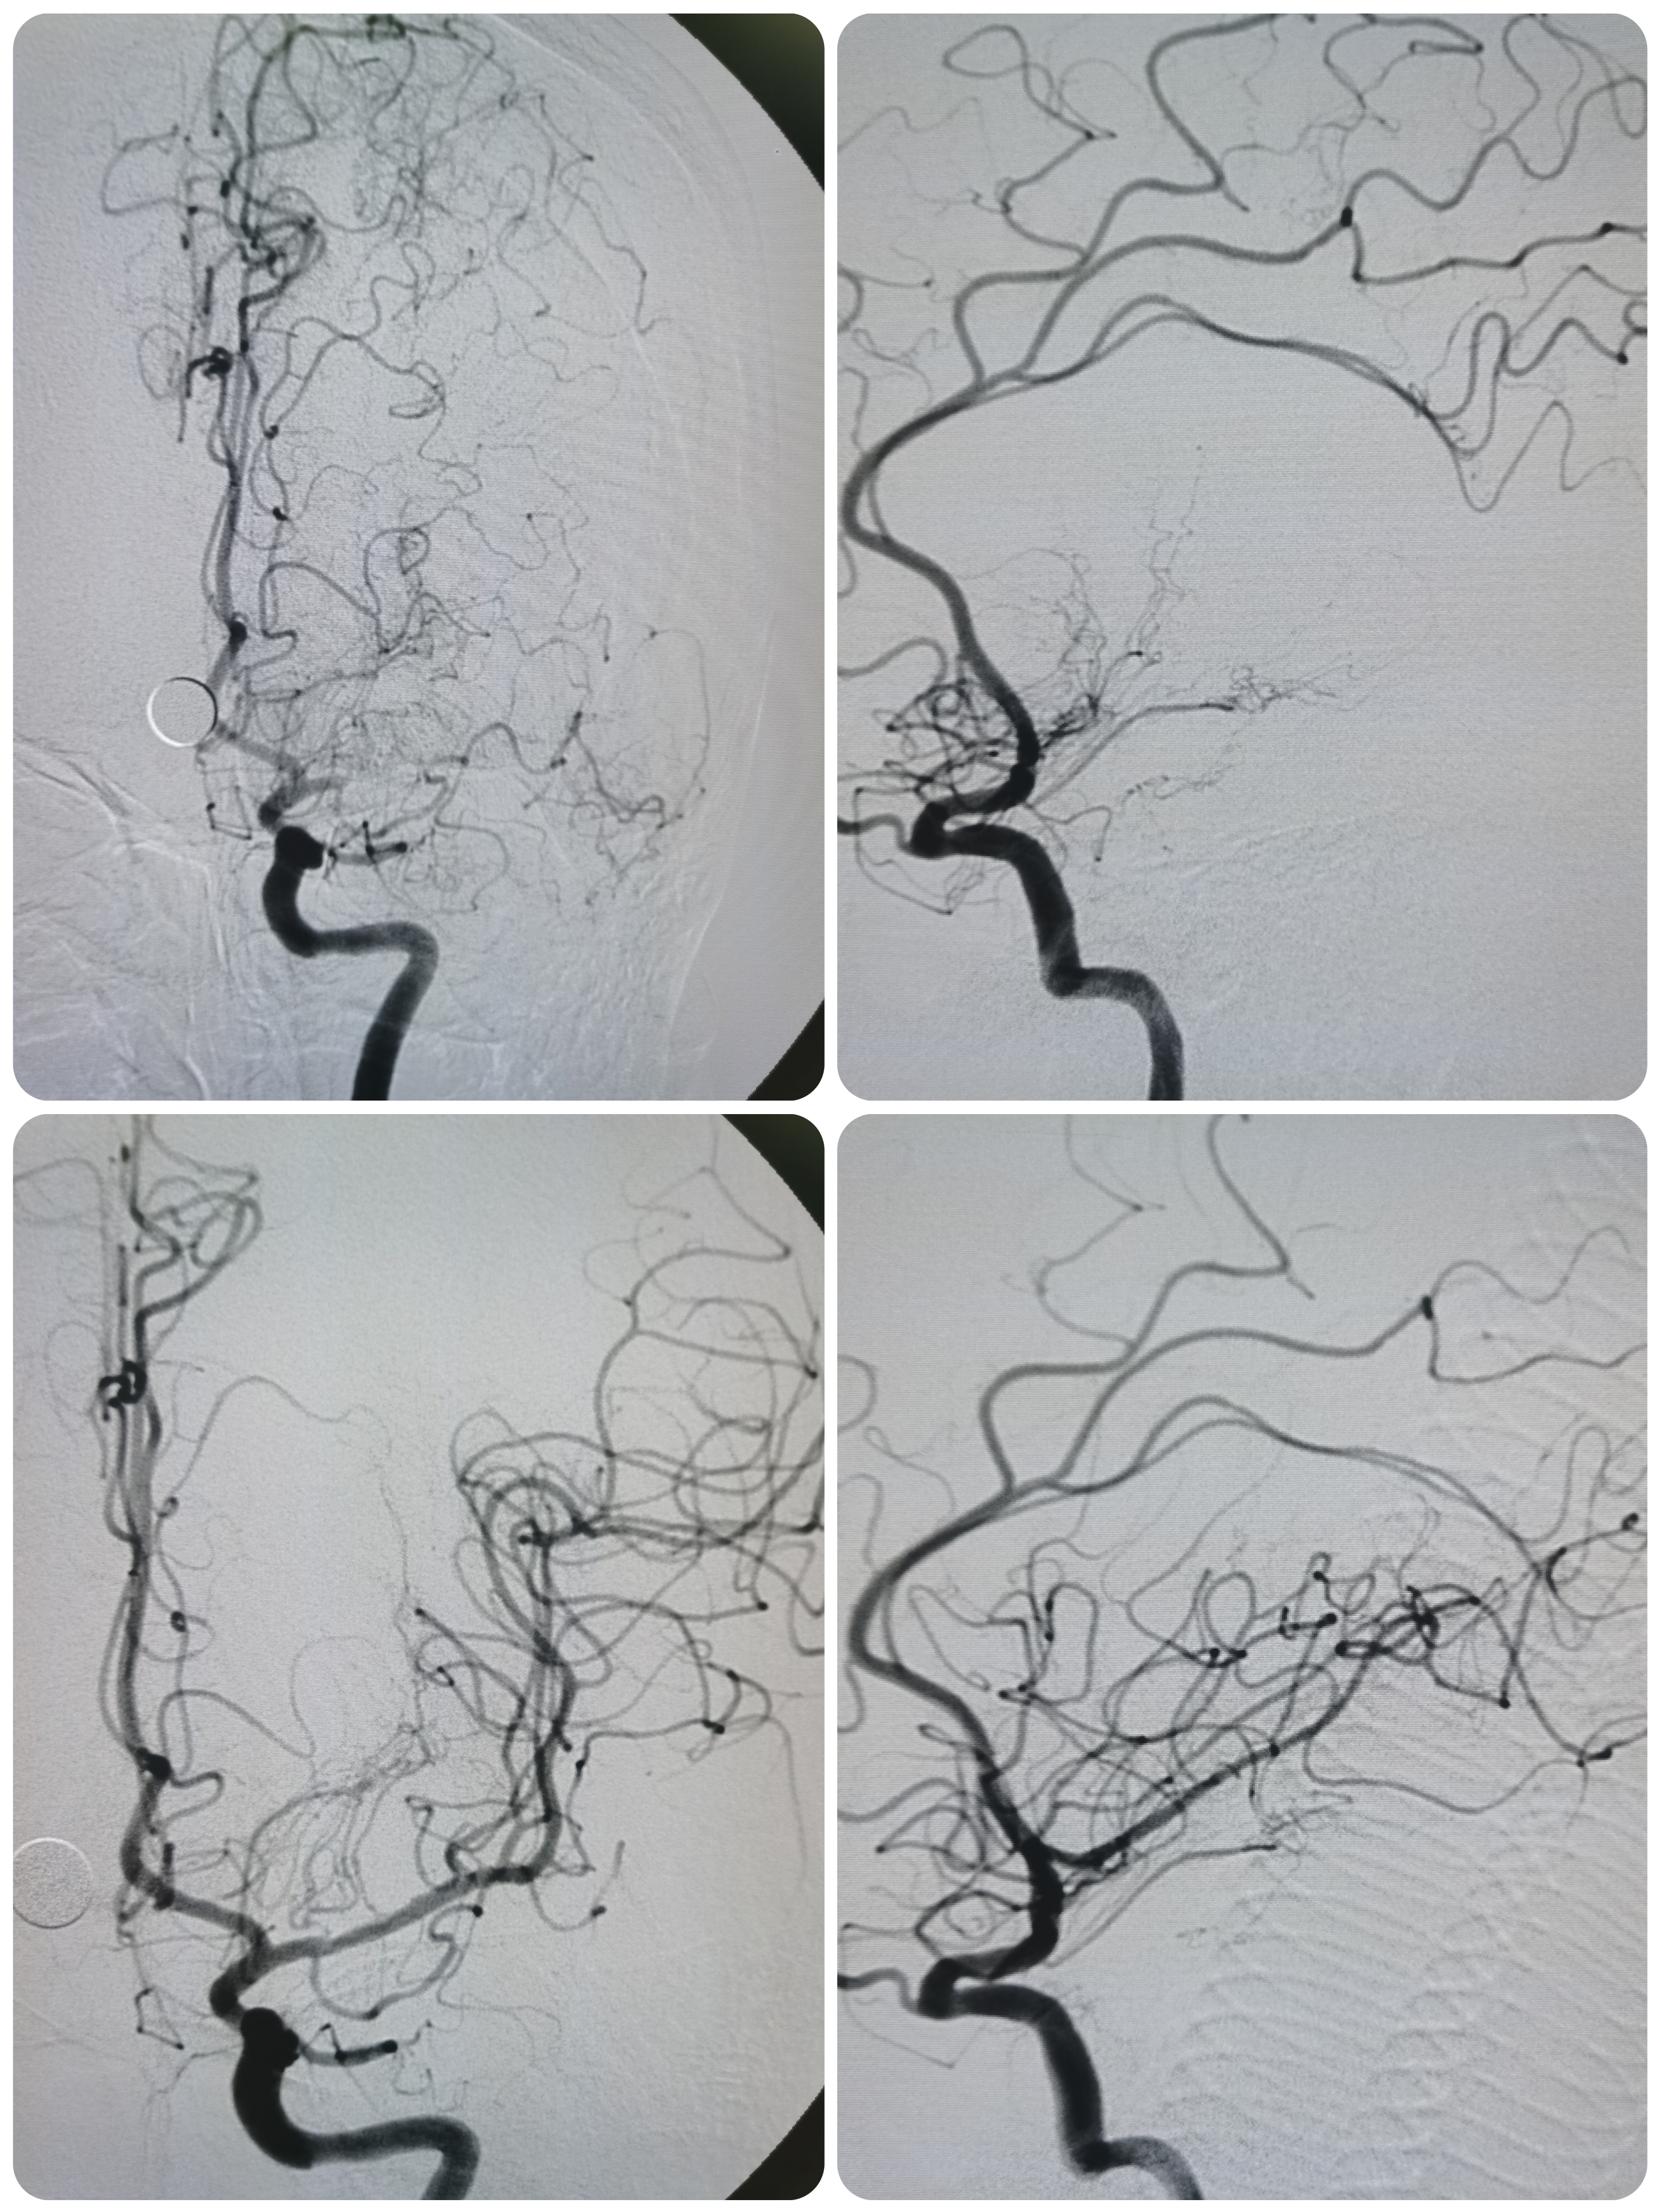

右椎动脉显影正常。

左侧大脑后动脉局部狭窄。

基底动脉显影正常。

左椎动脉显影正常。

右颈内动脉颅外段正常。

右颈内动脉颅内段显影正常。

右侧大脑中动脉M2局部狭窄。

左颈内动脉颅外段正常。

侧位见左侧大脑中动脉闭塞。

晚期可见左侧大脑中动脉返流。

正位见左侧大脑中动脉闭塞。

动脉晚期可见左侧大脑中动脉M2段返流。

1、本例患者系因左侧大脑中动脉急性闭塞出现左侧半球梗死,系责任血管。

2、造影评估见左侧大脑中动脉起始段闭塞,但动脉晚期可见远端血管返流显影,考虑闭塞段较短,且为新近闭塞,具备介入治疗指征。

3、球囊扩张后血管狭窄解除,无夹层及弹性回缩,遂未再植入支架,术后继续药物治疗,定期随访。